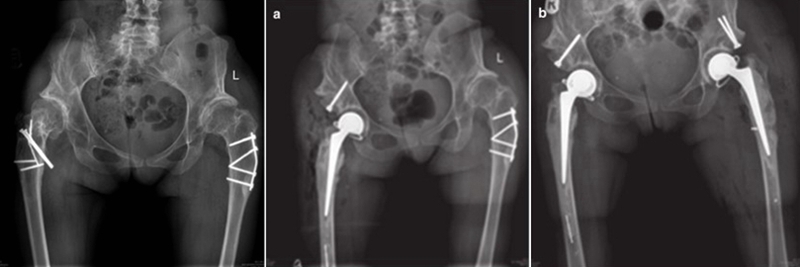

③近端的重建:纠正性截骨,短缩截骨。

纠正性截骨的要求是:

①在畸形最严重的部位纠正对线不良;

②最大限度保留骨质;

③截骨部位牢固固定;

④使用长柄假体跨越截骨端。

股骨截骨的不同方法:

股骨近端截骨重建——截骨方式:横形、斜形、阶梯式及双V形截骨

优点:不改变股骨近端的解剖,保持臀中肌附丽点完整,截骨后能矫正股骨的前倾角,是较为理想的股骨缩短方法。

缺点:①骨折——截骨两端捆钢丝;②截骨端不稳定,术后骨折不愈合——足够长的远端固定型非骨水泥型假体或组配型假体,假体长度足够,避免型号过小,必要时使用骨板加强固定;③失血多、时间长。